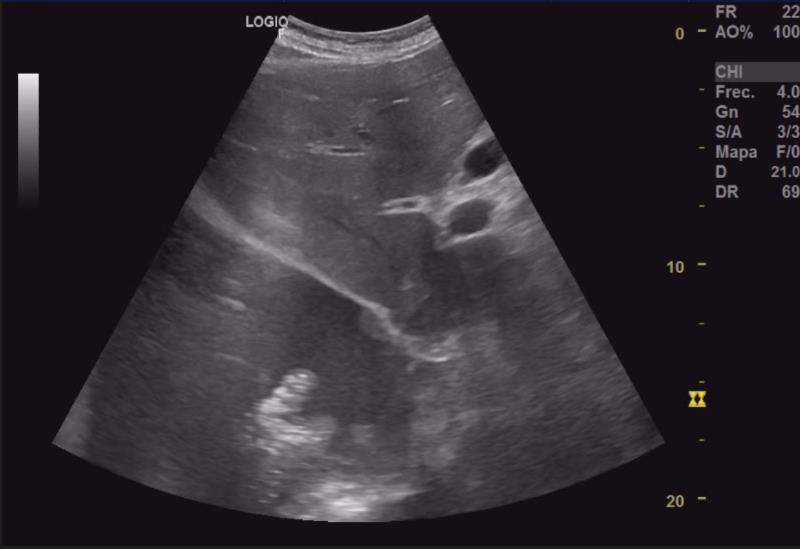

Hallazgos ecográficos

Importante colección anecoica supradiafragmática compatible con derrame pleural masivo (2/3 pulmón derecho), con flóculos ecogénicos (tongue-like sign) sugerentes de parénquima pulmonar atelectásico. Escasa colección anecoica pericárdica. Se identifica en riñón izquierdo una imagen heterogénea de bordes bien definidos en polo superior invadiendo pelvis, de unos 52x58x60 mm, con aumento de captación doppler.Pruebas complementarias